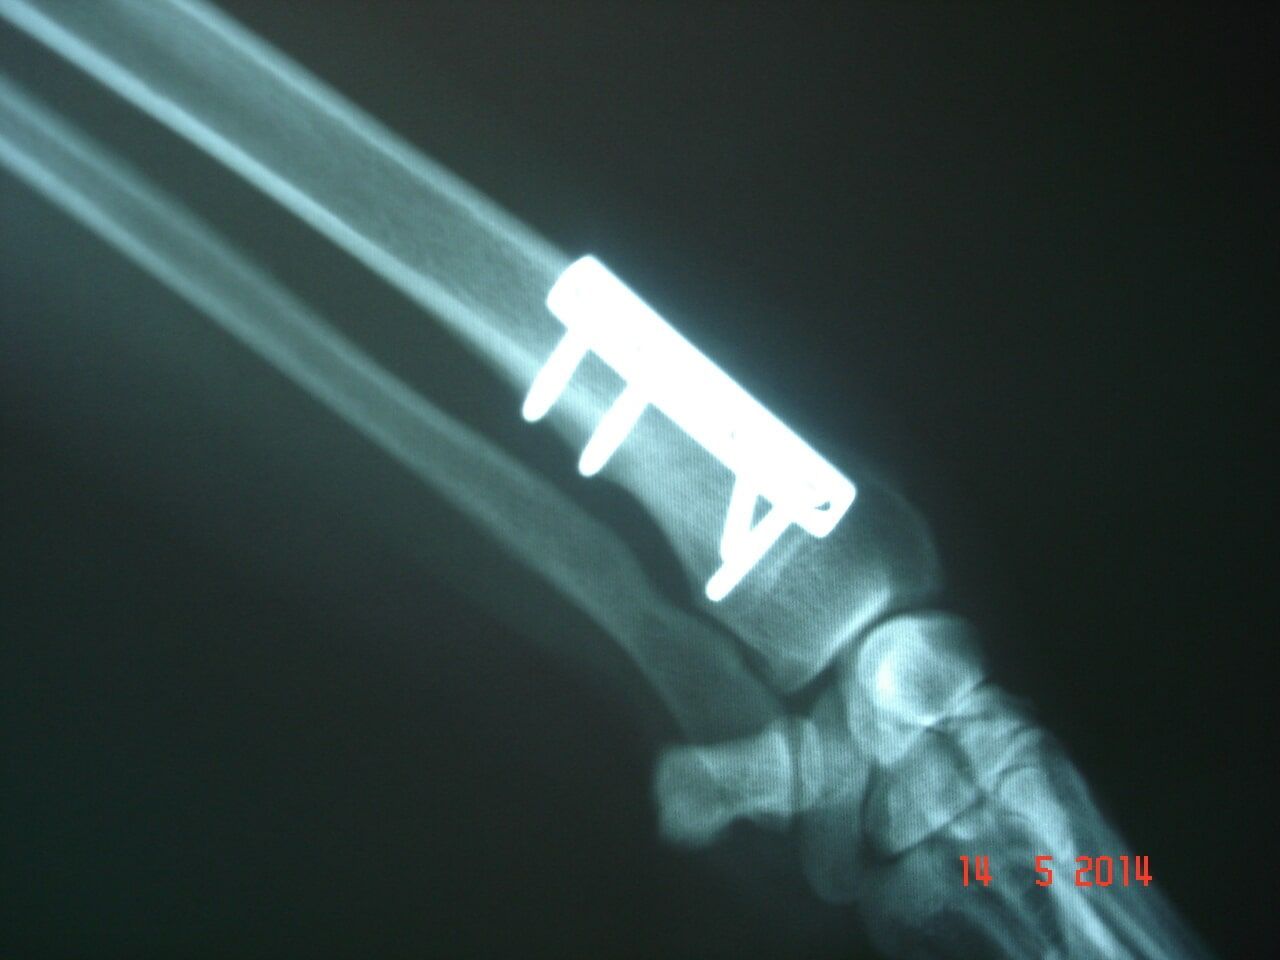

Χειρουργικές επεμβάσεις σκληρών μορίων (ενδεικτικά: κατάγματα, εξωτερική οστεοσύνθεση , ρήξη χιαστών, εξάρθρημα επιγονατίδας)